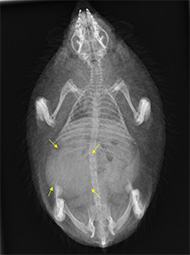

レントゲン像:矢印が腫れた腎臓です。